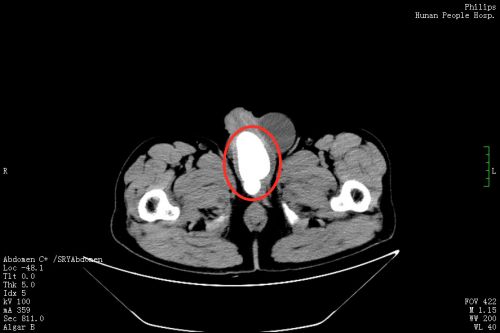

3月11日,刘先生在家人陪同下来到捷克论坛 泌尿外科门诊就诊,郭琼副主任医师接诊后,仔细询问病史并进行体格检查后发现,老人的左侧阴囊肿大,内有一个卵圆形的囊性肿块,符合“左侧睾丸鞘膜积液”的诊断。然而让医师惊讶的是,患者的绝大部分阴茎内都充满了坚硬的结节,压痛十分明显,高度怀疑是尿道结石。果然,泌尿系CT 检查发现,其膀胱尿道口和尿道内有一个鹅蛋大的结石,这正是导致老人持续会阴剧痛、尿频、尿急、排尿困难的罪魁祸首,随即将他收入泌尿三科病房。

郭琼副主任医师团队综合评估患者病情后,为他制定了“一石二鸟”的手术方案,一次手术同时解决尿道结石和睾丸鞘膜积液两个问题。322日,手术团队在全麻下为刘先生施行“左侧鞘膜翻转、尿道切开取石、尿道修补、膀胱镜检查、膀胱造瘘术”。在患者的后尿道及部分前尿道取出约10×8.1×4.5cm3大小重达256g,形态不规则、质地坚硬的结石。手术过程十分顺利,术中几乎无出血。